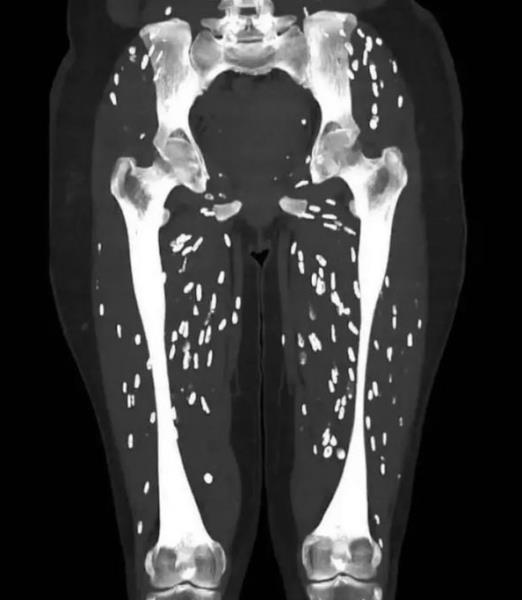

Одной из его последних публикаций была компьютерная томография, которую он назвал «одной из самых безумных», с которыми он когда-либо сталкивался. Снимок обнаружил многочисленные паразиты в ногах и в области таза пациента, симптомы цистицеркоза, тканевой инфекции.

Он продолжил: «Эти взрослые цепни затем откладывают яйца, которые, со своей стороны, выделяются с человеческими фекалиями. Очень важно отметить, что только тогда, когда эти яйца попадают в организм человека фекально-оральным путем, может развиться клинический синдром, известный как цистицеркоз. После того, как яйца попадают в организм (человека или свиньи), они выпускают личинки, которые проникают через стенку кишечника и попадают в кровь (через брыжеечные венулы), а оттуда могут распространяться буквально в любую точку тела. Мозг, глаза, подкожные ткани и скелетные мышцы являются самыми распространенными местами поражения. Личинки поселяются везде, куда попадают, и в результате образуют цисты, известные как цистицерки. Воспалительная реакция организма хозяина обычно приводит к гибели цист, которые впоследствии кальцифицируются, придавая им классический вид, который можно оценить на этом КТ-скане. Их обычно называют «кальцификатами рисовых зерен».